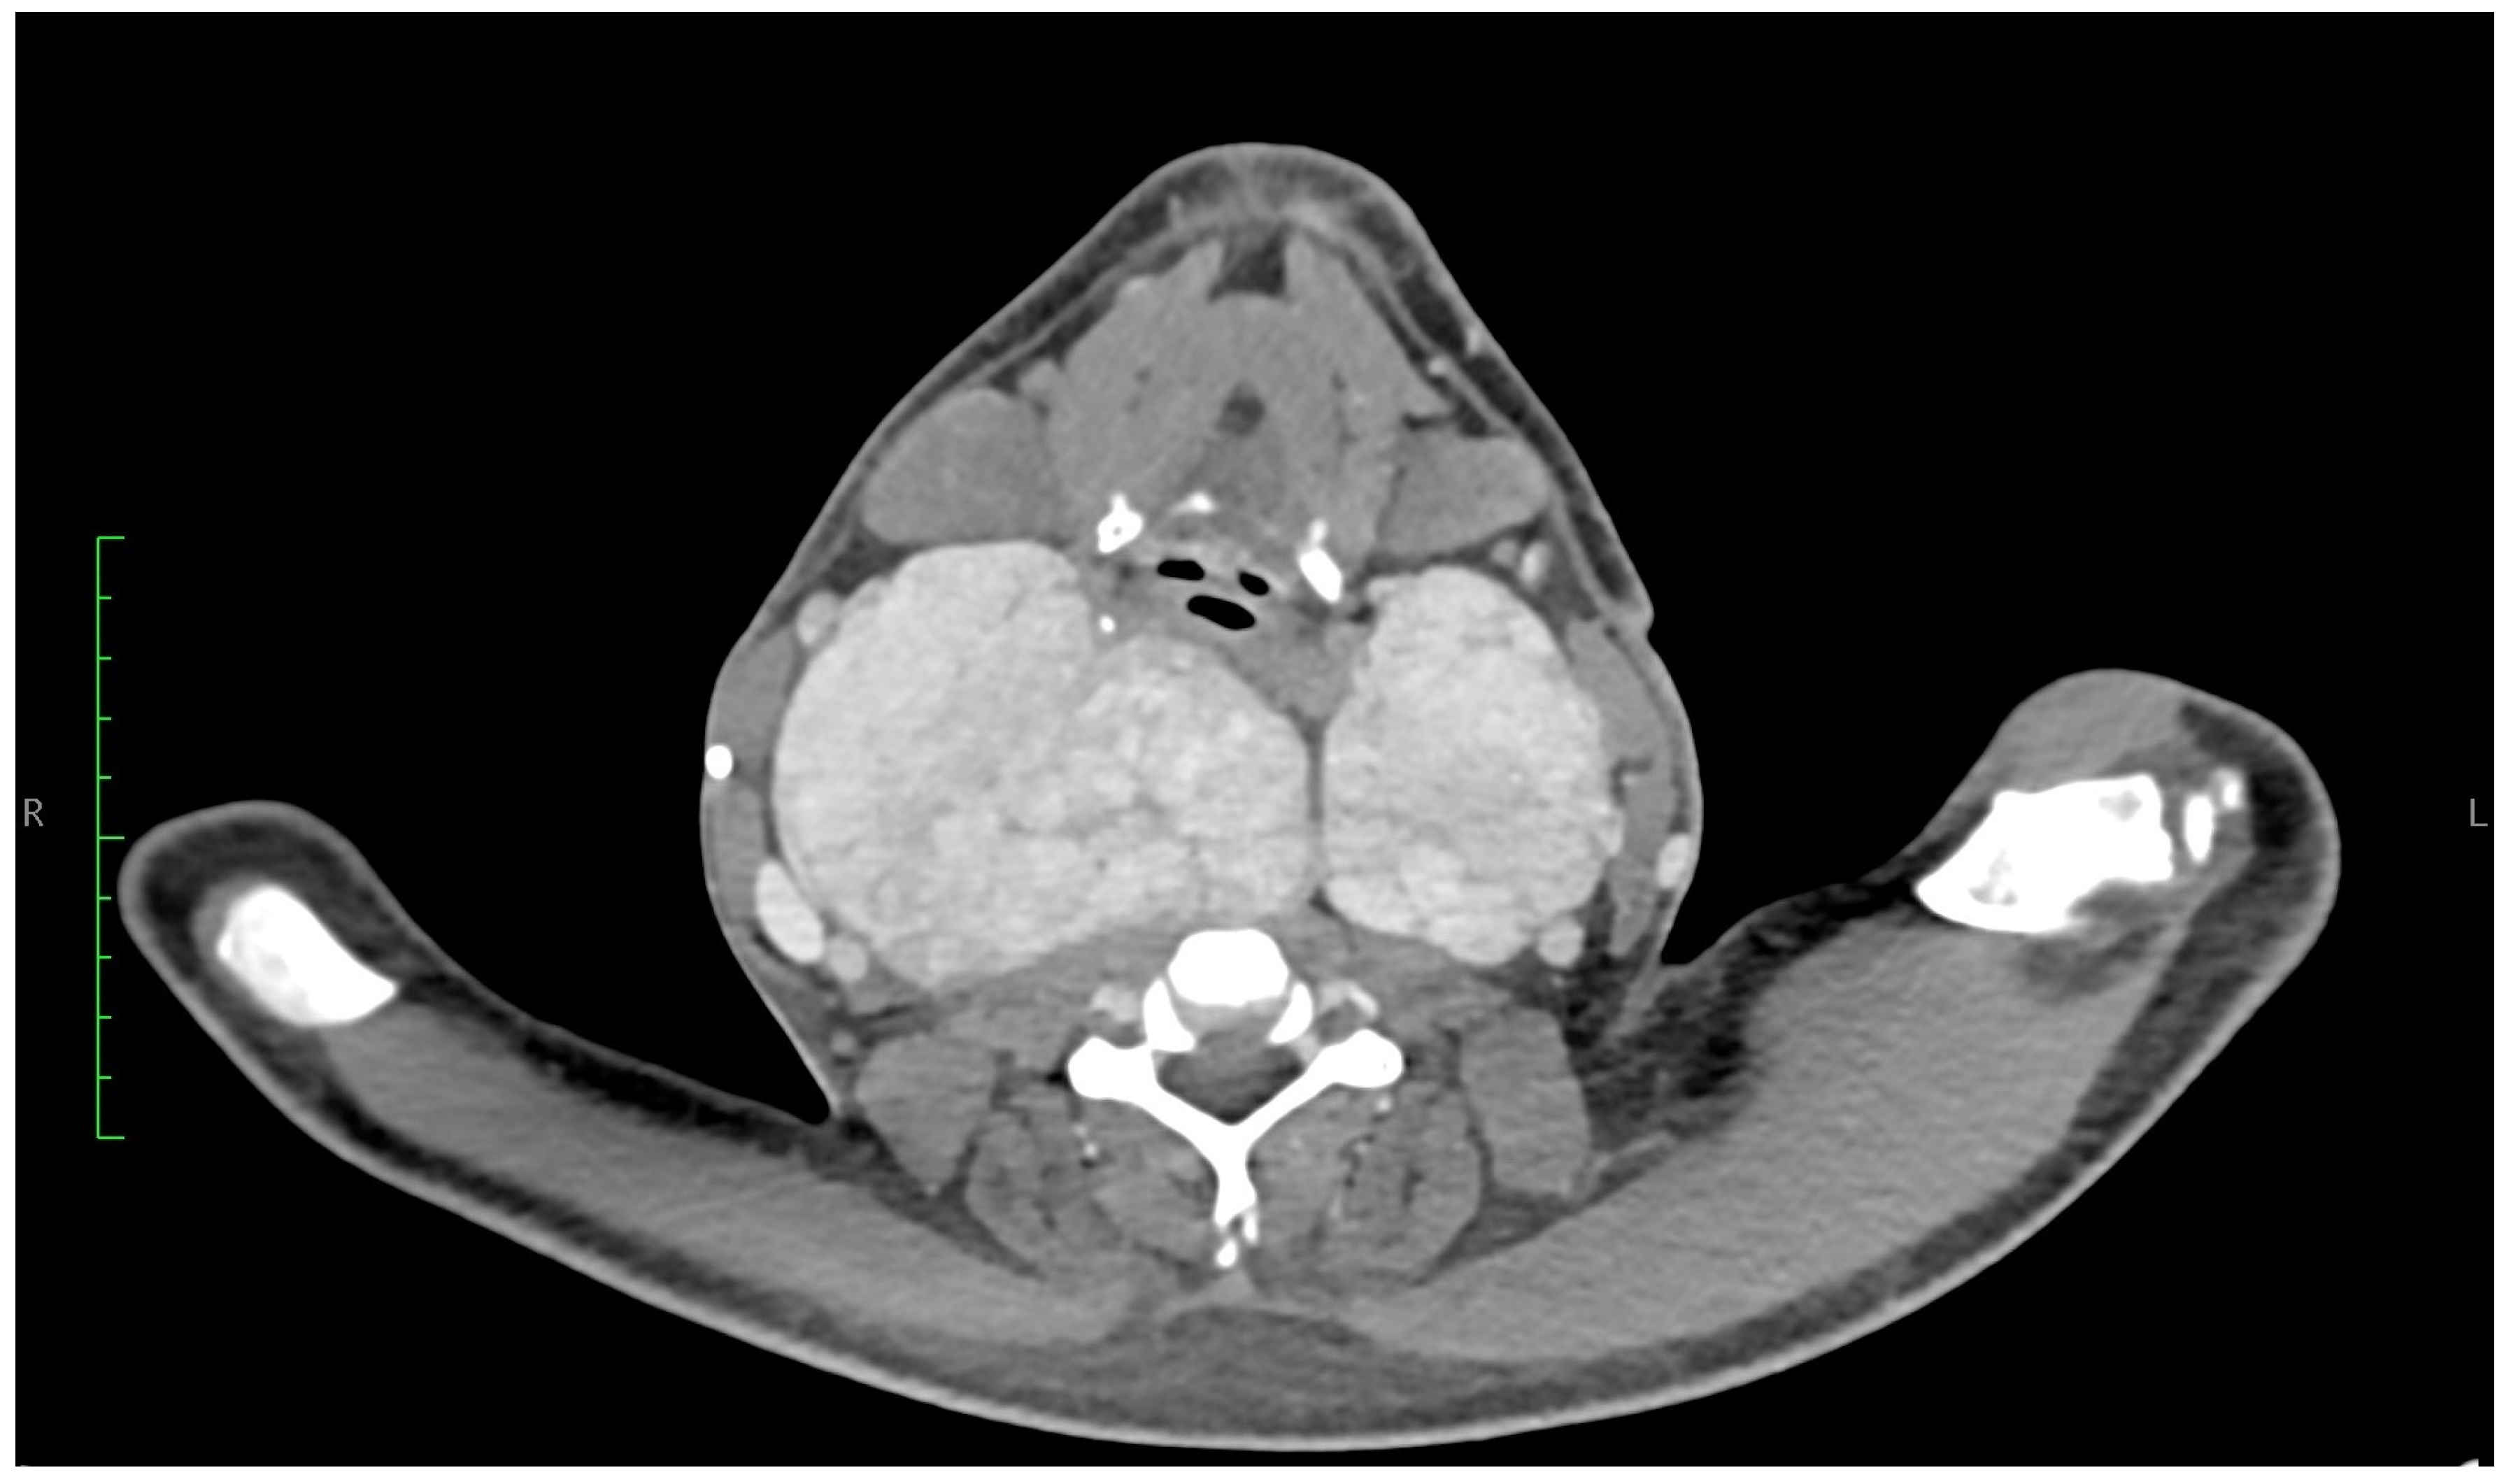

- Miyake, H.; Maeda, H.; Isomoto, I.; Nagatomo, H.; Nakashima, A.; Ashizawa, A. Computed tomography in amyloid goiter. J. Comput. Assist. Tomogr. 1988, 12, 621. [Google Scholar] [CrossRef]